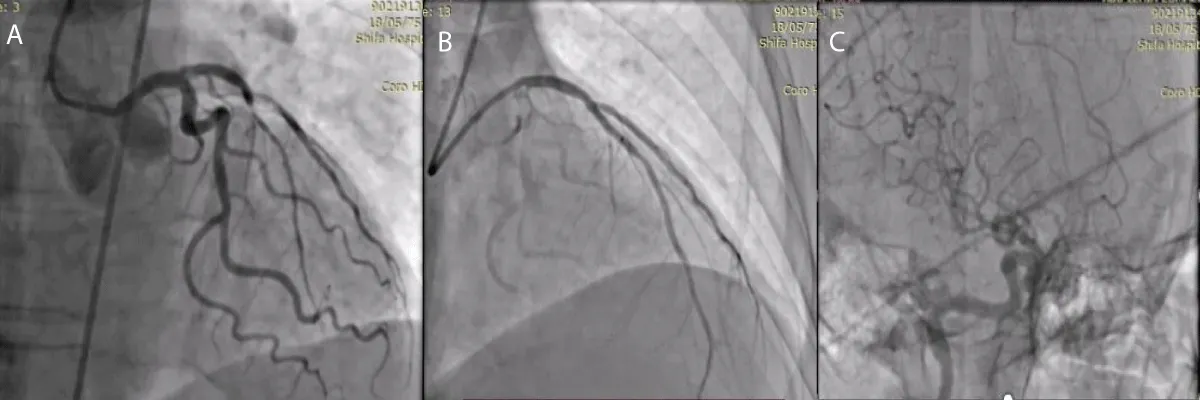

A 63-year-old male patient, previously healthy, hypertensive, diabetic and heavy smoker presented with acute burning chest pain radiating to both shoulders, which was associated with sweating and vomiting for 1 hour, but during hospitalization in the emergency room, he developed sudden onset of altered level of consciousness, dysarthria, nystagmus with National Institute of Health Scale Score (NIHS) score 12, after discussing the case we planned to do coronary and cerebral angiography. On examination the patient looks in pain, sweaty and tachypneic, and their blood pressure: was 75/40 mmHg, Electrocardiography was done and it revealed ST segment elevation in the anterior leads with ST-segment depression in I, II, AVF after that he received 300 mg of aspirin, 300 mg clopidogrel and norepinephrine 3 mcg/kg/min intravenous was started and urgently he was transferred to cardiac catheterization department for primary Percutaneous Coronary Intervention (PCI). During coronary angiography, it showed total occlusion of the proximal left anterior descending artery, stenting was done successfully by using resolute integrity 2.75 x 22 mm drug-eluting stent (Figure 2), then cerebral angiography showed normal anterior and middle cerebral circulation, but there was severe right vertebral artery stenosis, so angioplasty to vertebral artery was planned and it was done successfully (Figure 3), echocardiography was done and it showed reduced left ventricular Ejection Fraction about 30% - 35%, but no left ventricular thrombus was detected, then the patient was followed for 3 days at the hospital and he was discharged on Dual antiplatelet and he had mRS (0) with regular follow up at the outpatient clinic for 3 months, he had the good general condition and functioning well without any neurological deficit mRS (0).

Figure 2: A-coronary angiography shows proximal LAD total occlusion, B-after stent implantation in ostial LAD.

Figure 3: A- Cerebral angiography shows severe right vertebral artery stenosis, B- After successful angioplasty for vertebral artery.